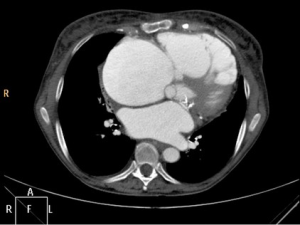

A 73-year-old female patient was admitted to our hospital with tricuspid valve (TV) regurgitation grade IV. Past medical history revealed previous mechanical mitral valve replacement and implantation of a pacemaker. Clinically she had typical signs of chronic congestive right heart failure. Massive edema of the lower legs were detected during clinical examination. Preoperative echo confirmed severe TV regurgitation and normal function of the mechanical mitral valve. Coronary artery disease was excluded by coronary angiogram. CT scan demonstrated massive dilatation of the right heart chambers. The right ventricle was in part stuck to the sternum (Figure 1). CT scan further showed “cirrhose cardiaque” due to chronic right heart congestion. She was referred for reoperation with TV repair or replacement.